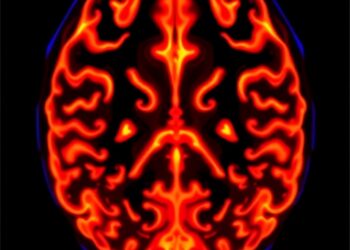

Novel Biomarker Enhances Assessment of Glioblastoma Aggressiveness

A groundbreaking advancement in the fight against glioblastoma, one of the most aggressive and deadly brain tumors, has emerged from ...